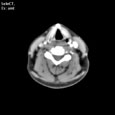

Критический стеноз правой внутренней сонной артерии. Критический стеноз правой внутренней сонной артерии

Пациент U., 69 лет

Критический стеноз правой внутренней сонной артерии.

ЦКБ5 Южной железной дороги, отделение лучевой диагностики.

На КТ-сканах шеи (до уровня основания черепа) в условиях ангиографического режима (в/в ультравист 300 - 100,0 мл 2,5 мл/сек.) определяется окклюзия правой внутренней сонной артерии на 15 мм дистальнее бифуркации общей сонной артерии, дистальнее контрастирование просвета артерии не определяется. Ассиметрично контрастированы яремные вены (справа интенсивность контрастирования значительно ниже).